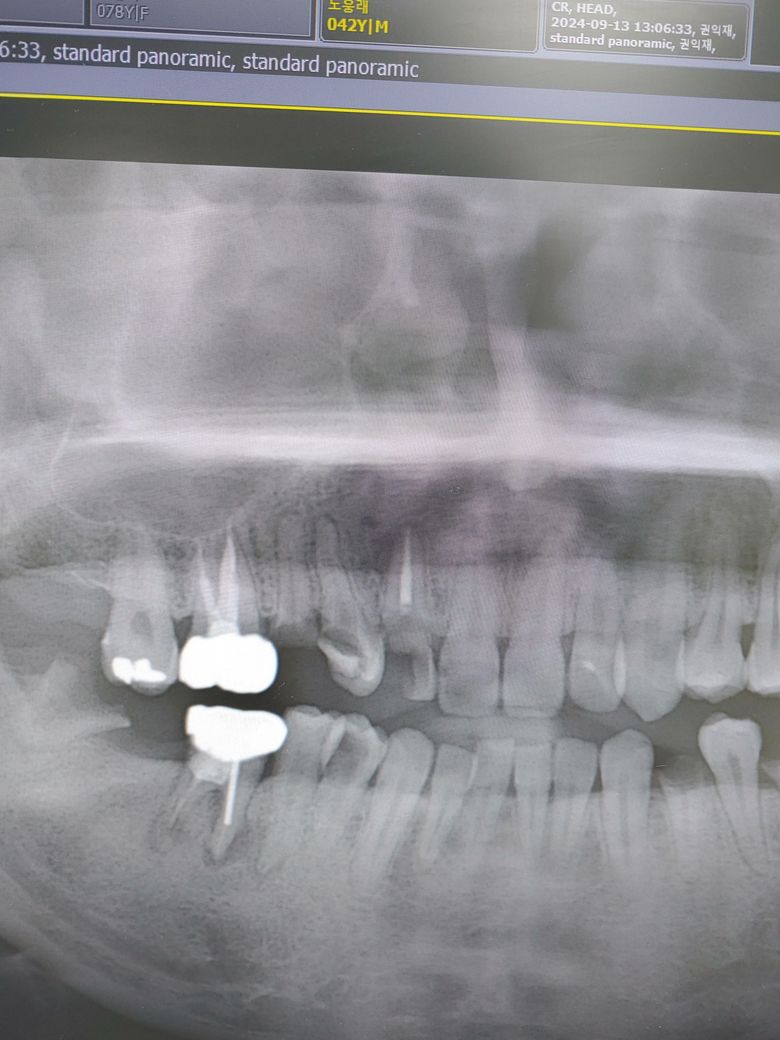

파노라마상에서 상악동염의 원인이 되었을 치아가 뭘까요?

안녕하세요 해당 파노라마상에서 상악동염의 원인이 되었을 확률이 높은 치아가 어떤 치아일까요?..............

사학동염으로 진행되기 위해서는 치근단 질환이 상악동 막을 뚫고 올라가 있는 경우가 많습니다. 사진으로 봤을 경우에는 16번이나 17번에 치근단 부위에 염증으로 인해서 상악동염이 생겨서 가능성이 높아 보입니다.

상악동염은 치아떄문에 생길수 잇지만 다른 원인이 잇을수도 잇습니다. 엑스레이 상으로 치아는 크게 문제가 잇어 보이진 않습니다.

상악동염의 원인이 되는 치아는 주로 상악의 소구치나 대구치 들입니다. 모두 가능성은 있어보입니다.